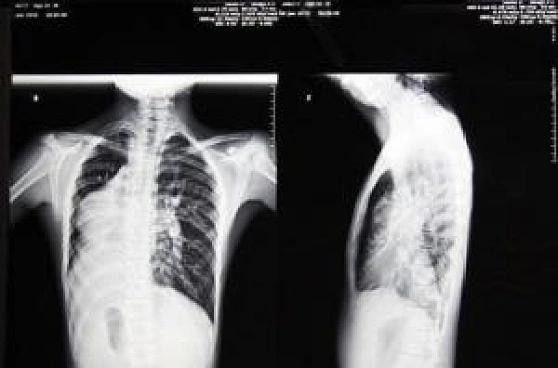

福建发现了一例罕见的“镜面人”,概率低到全球仅百万分之一,比中彩票头奖还难。患者陈先生因腹痛、皮肤发黄去检查,不仅有胆总管结石,还是右位心、完全内脏反位,脏器像照镜子一样长反了。当地医院一看片子,直说解剖结构全反,手术风险高做不了。 陈先生辗转多地,最后找到李海涛主任医师团队。手术时,腹腔镜画面都是“反”的,李海涛得逆向操作。不过他技术高超,巧妙避开变异血管,精准取净结石,仅用2小时,出血量不到50ml。医生也提醒,“镜面人”身体不适要早诊断早干预,降低手术风险。